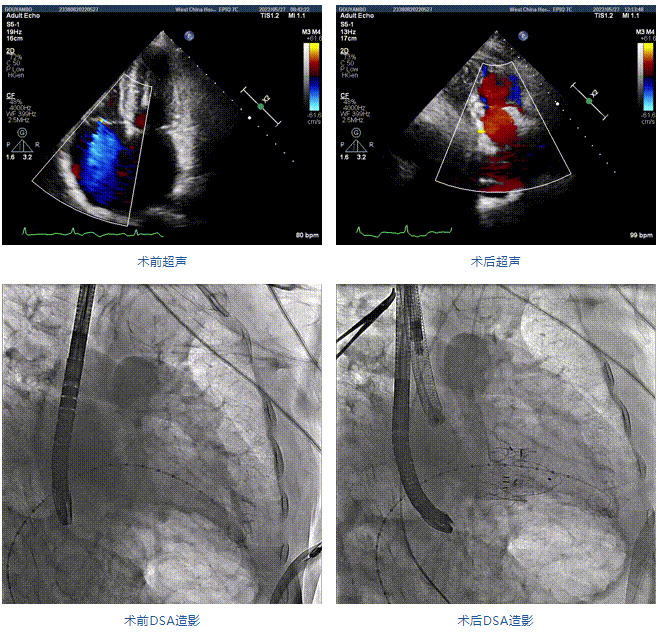

89歲男性。術(shù)前超聲報告顯示:雙房增大,左室壁肥厚,主、肺動脈增寬,三尖瓣重度反流。

團隊前期經(jīng)過多次討論,制定了周密的手術(shù)策略和預(yù)案。由于患者已是近九旬的超高齡老人,傳統(tǒng)外科開胸手術(shù)風(fēng)險極高,純介入經(jīng)血管三尖瓣替換能夠明顯減少創(chuàng)傷。術(shù)中陳茂及馮沅教授結(jié)合體表定位在造影指示下精準穿刺右側(cè)頸靜脈并預(yù)置兩把血管縫合器。成功建立經(jīng)皮血管入路后在食道超聲和DSA的引導(dǎo)下順利完成人工瓣膜植入,術(shù)后超聲和造影顯示人工三尖瓣同軸性良好,瓣架固定牢靠,無反流和瓣周漏,平均跨瓣壓差降為1mmHg。術(shù)畢收緊預(yù)置的血管縫合器縫線完成止血,縫合效果滿意,在手術(shù)室即刻拔除氣管插管。